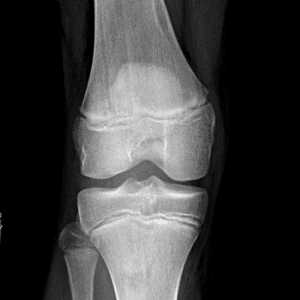

Pediatric Radiographs